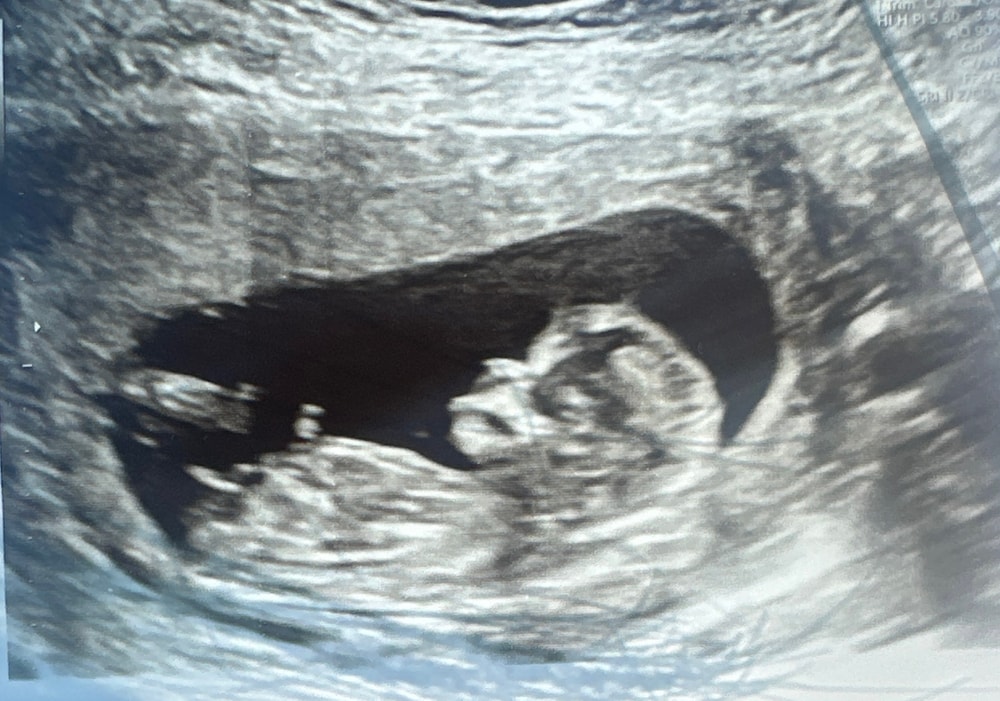

УЗИ 12 недель 2 дня.

Пол малышаКак думаете кто живет в животике ? Девочка или мальчик ?

через 2 недели пойду еще раз на узи ,надеюсь уже скажут точно кто

Yulianna , ну по бугорку в посте параллельно расположен, так что девочка. Но половые органы формируются еще, так что если он не поднимется, то точно девочка))) но я вообще не эксперт в этом, просто предполагаю))) надеюсь, что ваше желание исполнится, но и мальчик тоже счастье))) пусть главное здоровенький малыш будет)))

Yulianna , а я мальчика у вас вижу, но это бы еще побольше картинок. Тут угол наклона чуть острее, чем прямо. Вам фотку удачную дали, гадай не хочу

Лёля, у меня в первую беременность в 12 недель уже с уверенностью сказали что девочка та и было ,а в этот раз у этой же узистки была но она сказала что не хочет спешить с выводом кто ,сказала через неделю две прийти и скажем мне на 200 процентов кто там

Нина Т, согласна ,оно конечно любопытство есть ,но можно и подождать пусть подрастет .мне в первую беременность сказали пол в 11.5 недель а в этот раз сказал врач что не уверен и лучше подождать